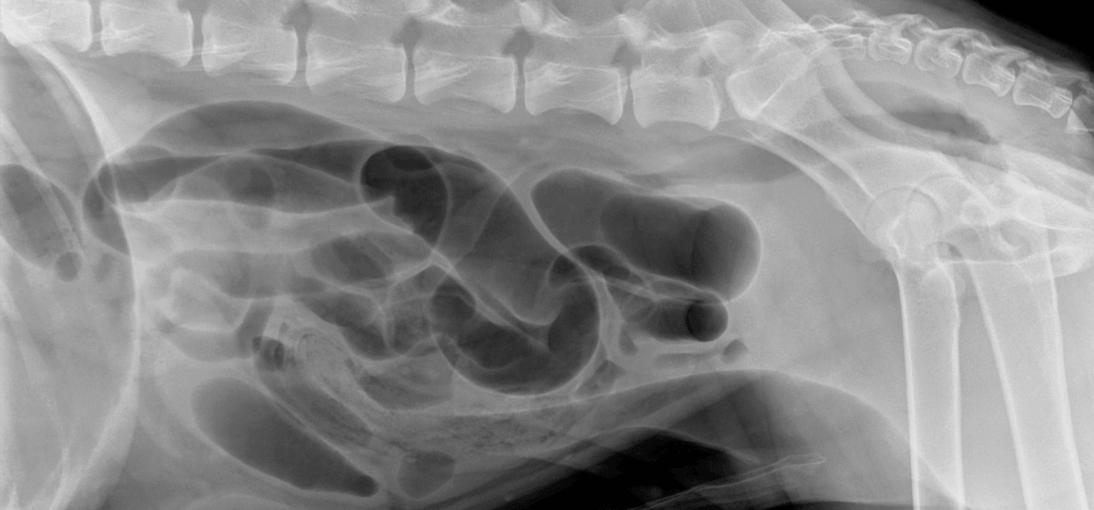

The AI screening immediately flagged the gastrointestinal crisis. Segments of small intestine showed clear mechanical obstruction: distended loops with gas and fluid accumulation. The stomach remained moderately distended with gas despite 12 hours of treatment. The AI also noted possible colitis and gastroenteritis, painting a picture of a GI tract under severe stress.

- Persistent to mildly progressive moderate segmental dilation of multiple small intestinal segments

- Small intestinal segment in mid left abdomen containing semitextured soft tissue opaque material (similar position compared to prior study)

- Stomach moderately distended with gas, slightly decreased from prior but still significant

- Colon unable to be traced throughout, likely due to fluid accumulation

- Narrow caudal vena cava on all images, likely indicative of hypovolemia

Persistent segmental small intestinal distention most compatible with mechanical obstruction secondary to foreign body (e.g., cloth). The narrow caudal vena cava suggested Max was becoming hypovolemic despite 12 hours of IV fluids, meaning he was losing fluids faster than they could be replaced.